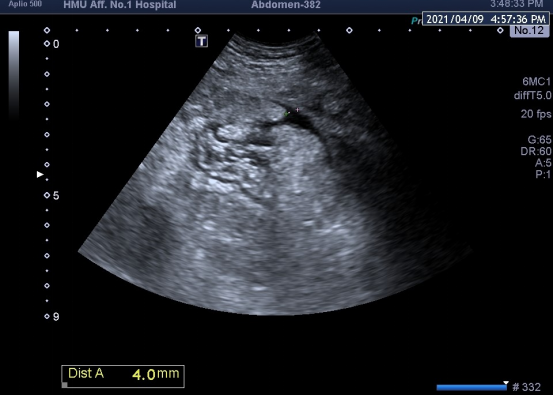

汤某,男,30岁,腹胀1月余,经反复治疗未见好转后来医院就诊,超声检查提示患者胆囊穿孔伴胆囊周围包裹性积液,此时患者已出现明显腹膜炎症状,经普外科会诊,该患精神萎靡、基础状态差,无法耐受手术风险,但此时如果不积极进行处置、减轻患者炎症反应,可能会导致其病情进一步加重、甚至危及生命。超声于下腹发现微量积液,因无法明确积液性质,史立君、徐丹联合杨秀华经MDT后决定进行超声引导下腹腔穿刺置管,鉴于穿刺进针路径极窄,仅为4mm,需要极精准快速的操作手法,杨秀华在超声引导下精准置入穿刺针并成功引出脓液,日均积液引流量约为1000-1500ml,积液引出后患者腹胀症状迅速减轻,状态明显好转,患者目前状态平稳,现已出院。

杨秀华介绍,随着精准医疗的日益发展,超声引导下介入治疗因其实时、精准、灵活、无辐射等优点日益受到临床科室的重视,在患者疾病的诊疗过程中发挥着重要作用。在该患者诊疗过程中采用的超声引导下腹腔穿刺置管引流技术为超声引导下微创治疗的常规操作,“大胆”、合理、灵活、精准的操作是本次疾病诊治的重要原则与亮点。ac米兰官网中文网站一院腹部超声室目前开展包括腹部、浅表、心脏、外周血管、小儿、妇产、肌骨、腔内直肠及肛管、胃肠的超声诊断,此外,还开展各种脏器的超声造影诊断、术中超声、超声引导下各种脏器及疾病的介入诊疗工作,仅射频消融年治疗量千余例,在重症胰腺炎治疗、胆囊造瘘、肝内胆管置管等技术上有丰富的临床经验,在国内享有盛誉。